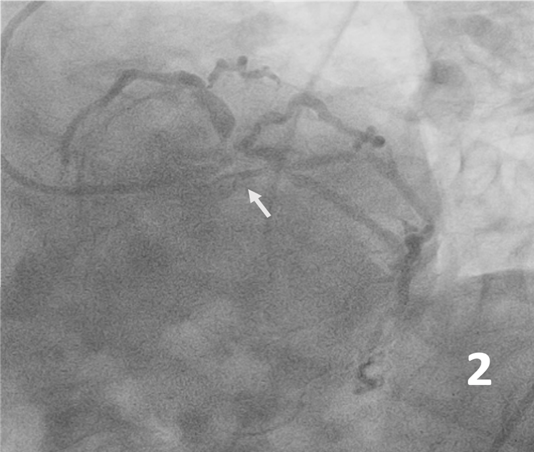

A 66-year-old male Jehovah’s Witness arrived at the emergency room having experienced typical persistent angina. Upon arrival, he was hemodynamically unstable. Electrocardiogram showed a high-risk pattern (Figure 1) and hs-cTn of 21 000 ng/L. Coronary angiography showed critical left distal main disease with trifurcation lesion to the left anterior descending artery (LAD), ramus intermedius, and left circumflex artery (LCx) (medina 1-1-1-1), and an 80% lesion in the middle segment of the LAD (Figure 2, 3). After medical consensus with surgeons, we decided to proceed with percutaneous coronary intervention.